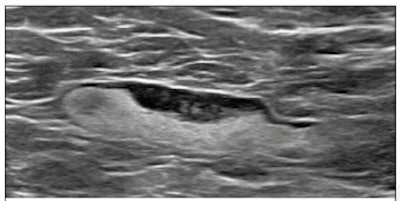

A 55-year-old woman who underwent screening mammogram and ultrasound seven days after her first COVID-19 vaccination dose. Screening mammogram and ultrasound demonstrated unilateral left axillary lymph node with cortical thickness of 5 mm on ultrasound (not shown). BI-RADS category 0 was assigned. Ultrasound from diagnostic workup performed seven days later showed no change in lymph node size. BI-RADS 3 was assigned.

A 55-year-old woman who underwent screening mammogram and ultrasound seven days after her first COVID-19 vaccination dose. Screening mammogram and ultrasound demonstrated unilateral left axillary lymph node with cortical thickness of 5 mm on ultrasound (not shown). BI-RADS category 0 was assigned. Ultrasound from diagnostic workup performed seven days later showed no change in lymph node size. BI-RADS 3 was assigned.Scanning axilla during screening and diagnostic breast examinations with high-frequency, linear-array ultrasound transducers is the protocol at UCLA Health, Mortazavi noted. That isn't true at all institutions (there are different approaches), but it proved to be a second important advantage in this case, she said.